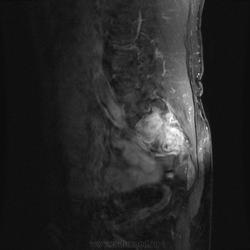

Мужчина, 60 лет. Направлен на МРТ пояснично-крестцового отдела позвоночника для исключения грыжеобразования. Жалуется на боли в правом тазобедренном суставе. Боли начались около месяца назад, сначала проявлялись в виде "неудобства", затем постепенно усиливались. В данный момент при объективном осмотре бережет ногу, хромает. Травмы, воспалительные заболевания отрицает.

При МРТ пояснично-крестцового отдела обратил на себя внимание крестец. Досмотрели крестец с контрастом. Хотелось бы услышать Ваше мнениие по поводу представленных снимков:

А по текущему случаю предложения будут? Не смущает ли кого-нибудь неровный косо-вертикальный гипоинтенсивный сигнал, в особенности заметный на постконтрастных корональных изображениях?

Я все-таки склоняюсь к стресс-перелому (что и указал на первом месте в заключении). Пытал товарища, он признался, что на даче поднимал какие-то тяжести. Онкологией не страдает, да и ничем в общем-то не болеет.